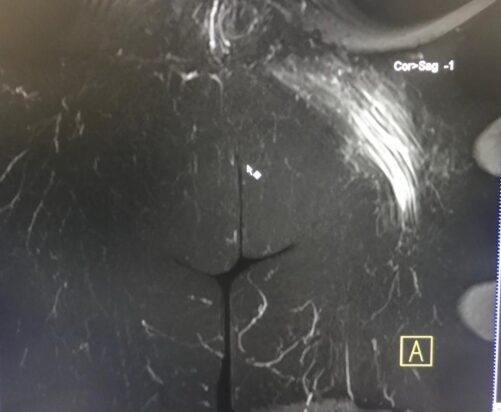

La RM es esencial para el diagnóstico de la topografía, severidad y extensión de los desgarros musculares.

Un compromiso fibrilar mayor del 15% del área muscular con una longitud superior a los 13cm y una localización central al vientre muscular , presenta un peor pronóstico y mayor tiempo de rehabilitación.

Un diagnóstico temprano es fundamental para evitar la retracción muscular y la formación de tejido cicatrízal.